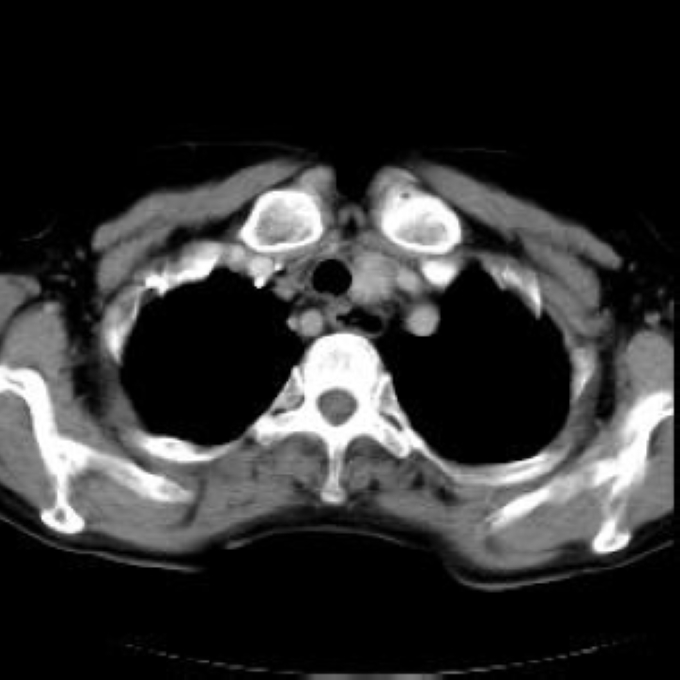

Arteria lusoria.

56 year old patient with dyspagia. A tumor of soft tissue was described in upper mediastinum on plain X-ray of the thorax. What is this mass in the upper mediastinum?